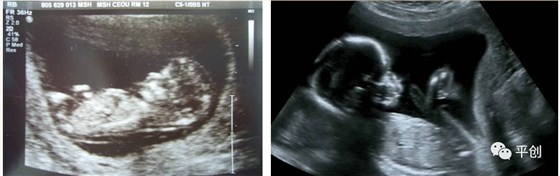

更準確的醫學診斷,來自B超檢查結果的輔助,準確的B超檢查結果,來自B超醫生看到的B超圖像,清晰的B超成像,來自好的耦合劑。所以說,好的耦合劑對B超的成像很重要。

而影響B超檢查成像的因素有兩點,一是來自好的探頭,二是來自優質的耦合劑。如果這兩個產品其中有一個質量不過關,即對B超成像有一定程度的影響,可能會有成像不清楚,醫生無法準確判斷所檢查器官的實際病變,嚴重的有可能度至醫生誤診的后果。

我今天要說的是:耦合劑對B超成像的影響。